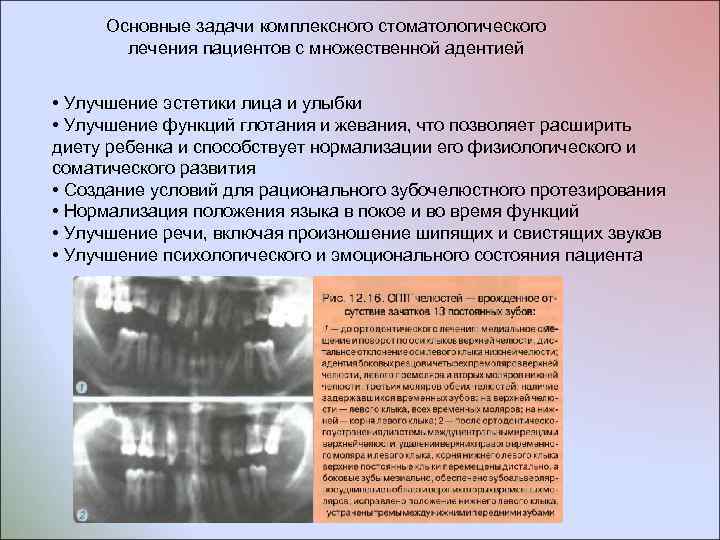

Врожденное отсутствие отдельных зубов, их множественное отсутствие и последствия Клиническое обследование не позволяет с уверенностью констатировать адентию отдельных зубов и дифференцировать ее с ранней их потерей или ретенцией. Более информативно рентгенологическое обследование челюстей, а именно изучение их ОПТГ В связи с внедрением в практику метода ортопантомографического исследования челюстей появилась возможность изучать степень формирования и рассасывания корней временных зубов, соотношение этих зубов с соседними и противостоящими зубами, длительность задержки временных зубов после периода их физиологической смены. Сроки смены временных зубов постоянными различны в их отдельных группах: смена резцов в норме происходит в возрасте 7 -9 лет, моляров 911, клыков 10 -2 лет (на верхней челюсти смена всех временных зубов заканчивается обычно на полгода позже, чем на нижней) Задержавшимися считаются те временные зубы, которые находятся в зубных рядах через 2 года после периода их физической смены

Врожденное отсутствие отдельных зубов, их множественное отсутствие и последствия Клиническое обследование не позволяет с уверенностью констатировать адентию отдельных зубов и дифференцировать ее с ранней их потерей или ретенцией. Более информативно рентгенологическое обследование челюстей, а именно изучение их ОПТГ В связи с внедрением в практику метода ортопантомографического исследования челюстей появилась возможность изучать степень формирования и рассасывания корней временных зубов, соотношение этих зубов с соседними и противостоящими зубами, длительность задержки временных зубов после периода их физиологической смены. Сроки смены временных зубов постоянными различны в их отдельных группах: смена резцов в норме происходит в возрасте 7 -9 лет, моляров 911, клыков 10 -2 лет (на верхней челюсти смена всех временных зубов заканчивается обычно на полгода позже, чем на нижней) Задержавшимися считаются те временные зубы, которые находятся в зубных рядах через 2 года после периода их физической смены

Основные задачи комплексного стоматологического лечения пациентов с множественной адентией • Улучшение эстетики лица и улыбки • Улучшение функций глотания и жевания, что позволяет расширить диету ребенка и способствует нормализации его физиологического и соматического развития • Создание условий для рационального зубочелюстного протезирования • Нормализация положения языка в покое и во время функций • Улучшение речи, включая произношение шипящих и свистящих звуков • Улучшение психологического и эмоционального состояния пациента

Основные задачи комплексного стоматологического лечения пациентов с множественной адентией • Улучшение эстетики лица и улыбки • Улучшение функций глотания и жевания, что позволяет расширить диету ребенка и способствует нормализации его физиологического и соматического развития • Создание условий для рационального зубочелюстного протезирования • Нормализация положения языка в покое и во время функций • Улучшение речи, включая произношение шипящих и свистящих звуков • Улучшение психологического и эмоционального состояния пациента